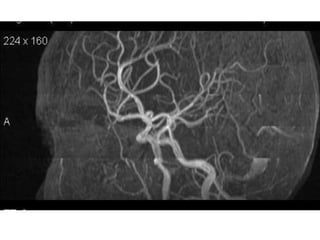

Arteries of the brain (lateral view) - MRA

1. Anterior cerebral artery

2. Anterior communicating artery

3. Basilar artery

4. branches (in insula) of middle cerebral artery

5. Cavernous portion of internal carotid artery

6. Cervical portion of internal carotid artery

7. Genu of middle cerebral artery

8. Intracranial (supraclinoid) internal carotid artery

9. Middle cerebral artery

10. Ophthalmic artery

11. Petrous portion of internal carotid artery

12. Posterior cerebral artery

13. Posterior cerebral artery in ambient cistern

14. posterior cerebral artery in interpeduncular

cistern

15. Posterior communicating artery

16. Posterior inf cerebellar artery.

17. Quadrigeminal portion of posterior cerebral

artery

18. Superior cerebellar artery

19. Vertebral artery